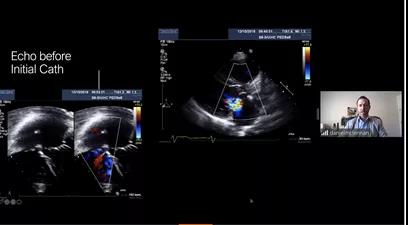

第二场会议首先由印度尼西亚心脏协会主席Radityo Prakoso教授向与会专家介绍有关零射线下进行MFO多功能封堵器植入的方法,并分享了全球首例在纯超声引导下成功植入MFO多功能封堵器的病例。此方法不仅可以确保患者得到安全有效的封堵治疗,还避免了患者及医护人员长期暴露在射线下,最大程度的减少了辐射伤害。

印尼Radityo Prakoso教授发言